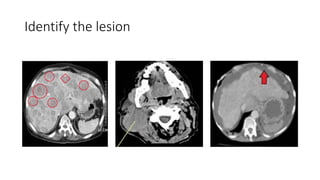

Identify the lesion

Target / non target lesions

• Target lesion :

• Maximum 5 lesions

• 2 lesions per organ

• Lesion with longest diameter

• Easy for repeated reproducible measurement

Editor's Notes

• #13 Must be accurately meaaured in atleast one dimension (longest diameter in the plane of measurement is to b recorded )